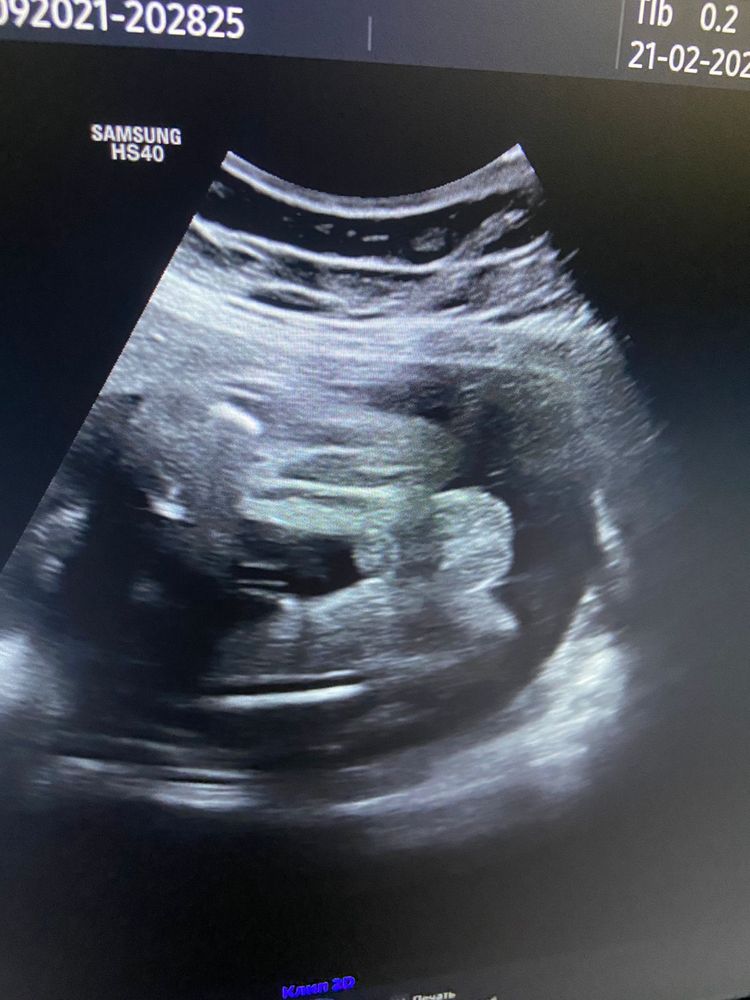

Девочки помогите 🆘 мальчик или девочка ? До 30 недель 4 разных врача утверждали что девочка ,узи на 17 неделе , а тут пошла на допплер и врач говорит что мальчик 👦 мы уже все вещи розовые купили 😅было ли у кого такое ? 30 недель снимок также прикладываю

Первое фото точно девка, а на втором скорее всего что-то примешалось, может пуповина. В общем, парнем пока не пахнет)

так писюн не видно, больше на губы похоже

На втором фото действительно похоже на мальчика. Прям мошонку хорошо видно и сам пистолетик. Напишите потом что скрининг покажет )